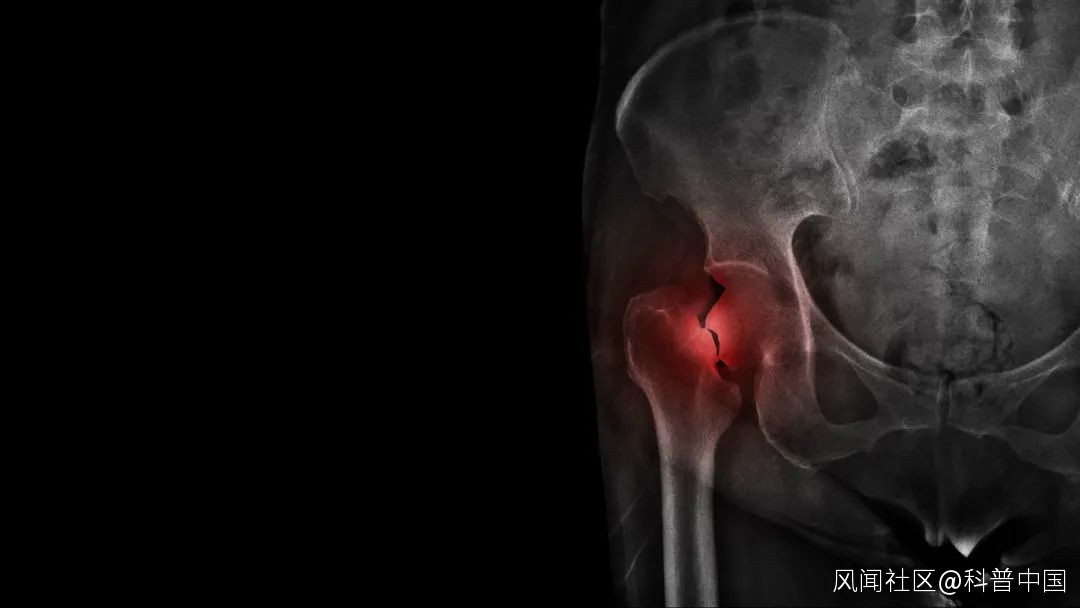

更年期女性內源性雌激素水平下降,不能抑制破骨細胞的作用,導致骨丟失加快,如果這期間鈣攝入不足,將會增加患骨質疏鬆的風險,進而易發生骨折,嚴重影響女性的健康。

早在 1984 年美國國立衞生研究院就召開了鈣與骨質疏鬆的研討會,將絕經女性鈣的每日攝入量從 800 毫克/天提高到了 1500 毫克/天。我國《更年期健康管理核心信息專家共識》中提到:女性在更年期每日應保證鈣攝入量 1000 毫克。

而牛奶及其奶製品可以增加絕經後女性的骨密度,包括脊柱、股骨頸、髖骨及全身骨密度。

隨着年齡的增加,骨量流失加快,老年人患骨質疏鬆的風險顯著增加。研究表明,2016 年我國 60 歲以上的老年人骨質疏鬆症患病率為 36%,其中男性為 23%,女性為 49%。

可別小看了骨質疏鬆,這病也能“要命”。美國、歐洲和日本大約有 7500 萬人患有骨質疏鬆,而病死率達到了 10%-24%,主要是髖骨骨折危害最大。